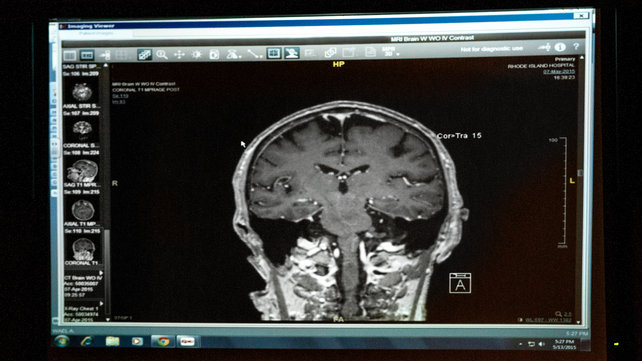

A new center has opened in Rhode Island to help diagnose an often misidentified disorder.

The neurology departments at Rhode Island, The Miriam, and Newport hospitals offer both inpatient and outpatient treatments.